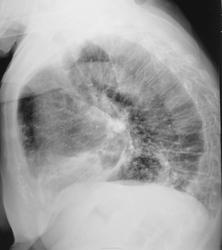

С подозрением на пневмонию направлена на рентгенографию ОГК.

Честно говоря, свежей инфильтрации не вижу. Легкие фиброзны, слева передне-базальные синусы облитерированы.

Возраст большой. Изменения сосудов в виде варикозных расширений, фиброз. В левом лёгком ,наверное, изменения в виде фиброза за счёт мелких тромбоэмболий. С сердцем проблем нет?

Согласна с фиброзными изменеиями и усиленным с/рисунком, структура корней нечеткая. И видится мне над куполом слева (в прямой проекции на фоне сердечной тени) газовый пузырь. Дала бы глоток бария.